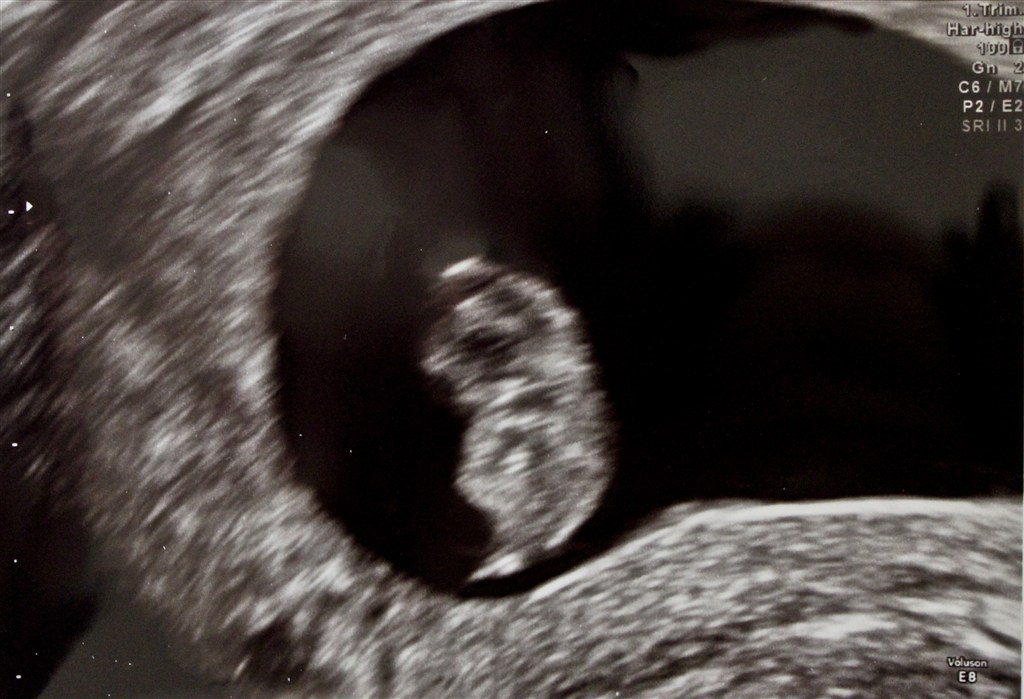

Desuden fik vi et par billeder af vidunderet, hvilket også var første gang!!

Ifølge målingerne er den 15 mm. og jeg går ind i 9. uge i morgen. Bliv hængende, lille spire!

Vedhæftede fotos (klik for at se i fuld størrelse)